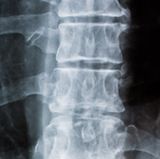

Für Kreuzschmerzen gibt es viele Ursachen: Bewegungsmangel und Stress im Job sind die wichtigsten Auslöser für die Pein. Zum Tag der Rückengesundheit sagen wir, was Sie besser vermeiden sollten.

Tag der Rückengesundheit Die zehn schlimmsten Dinge für die Wirbelsäule